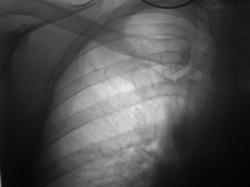

Иллюстрация 13. Фрагмент рентгенограммы правой половины грудной полости, произведенной в прямой стандартной проекции.

Неоднородное снижение прозрачности легочной ткани правой верхушки за счет слияния очагов лобулярной инфильтрации, местами с округлыми просветлениями. На фоне участков лобулярной инфильтрации дифференцируются отдельные очаги.

Справа на уровне головки корня дифференцируются «плотные» лимфатические узлы – «архив», в области тела корня дифференцируется гиперплазированный бронхопульмональный лимфатический узел неоднородной структуры.

В дополнении к вышеуказанному, справа картина сегментита, на фоне чего определяются множественные полостные образования.